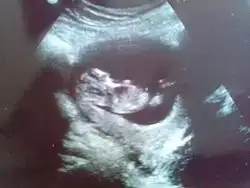

Gurbet ablam arkadasimin bebegi ALLA RIZASI ICIN BI BAKSAN KIZ MI ERKE MI? ustteki iki resim bugunku goruntuler en alttaki 6 hatalikken

Ben erkek diyorum canim facede yazmistim ama kaldrmislarneyse belli oldugunda buradan bize haber edersen sevinrim ins oglusu geliyodr iyi dusunsun iyi olsun gonlundekine kavsu r ins

Insallah erkektir, zeynepcim mutlaka haber vericem ama kizada benzettiler hayirlisi